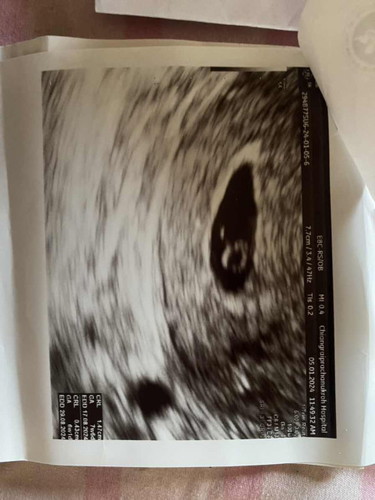

ท้อง8Wนับจากประจำเดือน

อันตราซาวต์มาหมอบอกว่าท้องลมงงมากท้องลมเหมือนมีตัวอยู่ข้างในตอนนี้เครียดมากค่ะหมอนัดซาวต์อีก1อาทิตย์ยังไม่มีตัวหัวใจต้องยุติการตั้งครรภ์

ของเราซาวด์แล้วเหมือนของคุณแม่เลยค่ะ เราซาวด์ตอน6สัปดาห์ถ้านับจากประจำเดือน ของเราคุณหมอบอกกลมๆข้างในคือไข่แดงนะคะ นัดอีกทีตอน10สัปดาห์ คุณแม่ไม่ต้องเครียดค่ะ ลองรอซาวด์ใหม่อีกทีอาจจะเจอก็ได้ค่ะเพราะอายุครรภ์มากขึ้นแล้ว